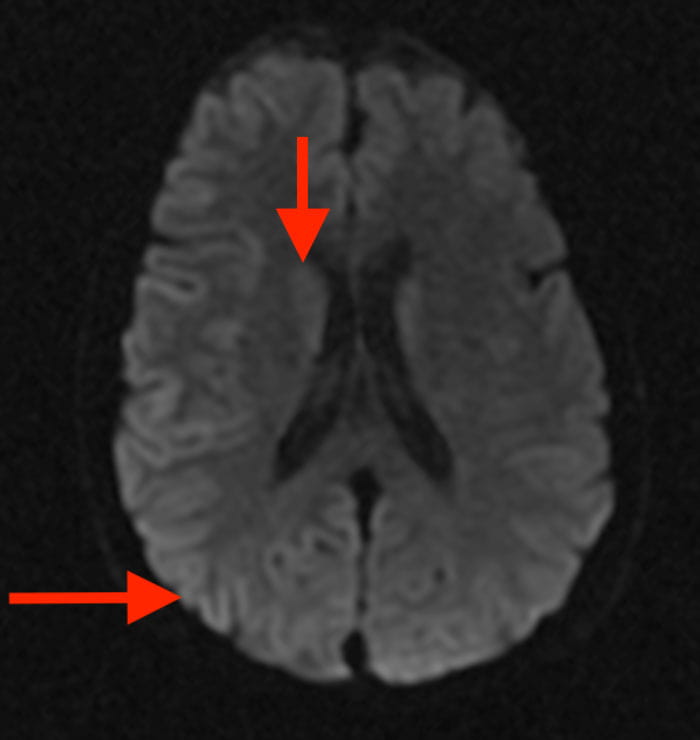

Approximately one to two new cases of prion disease occur per 1 million individuals worldwide, and it is invariably fatal. Also known as transmissible spongiform encephalopathy (TSE), the rare group of progressively neurodegenerative disorders is caused when normal prion proteins misfold and cluster together, resulting in debilitating neurological symptoms that include rapid dementia, unsteady gait, jerky movements and hallucinations. The time from onset of symptoms to death is usually between four and six months.